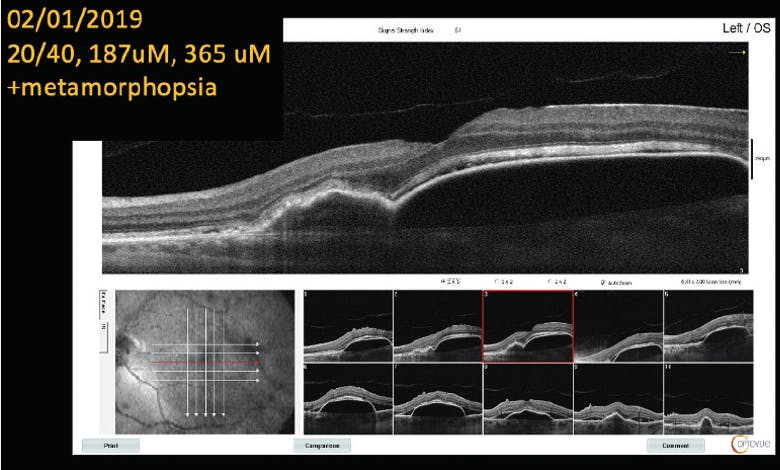

• Patient presented with 20/40 VA OS. Significant, symptomatic metamorphopsia was noted, associated with a large pigment epithelial detachment (PED; Figure 1).

<p>Figure 1. The patient presented with 20/40 VA, metamorphopsia, and a PED.</p>

Figure 1. The patient presented with 20/40 VA, metamorphopsia, and a PED.